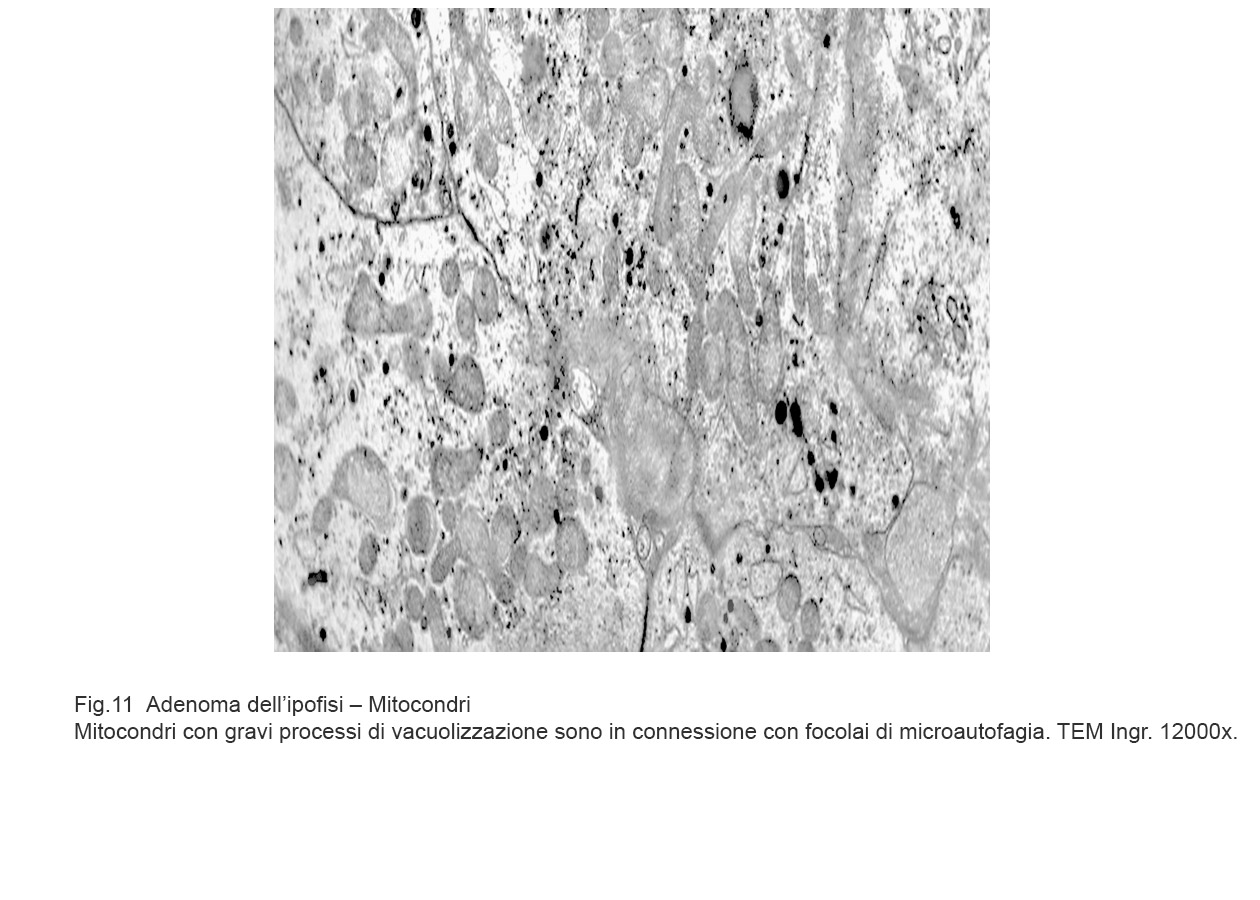

Mitocondri vacuolizzati commisti a focolai di micro-autofagia.

Fig.10